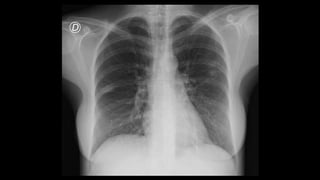

Una mujer de 31 años fue ingresada por faringoamigdalitis pultácea que no mejoró con tratamiento ambulatorio. Presentaba también molestias abdominales, náuseas, vómitos y diarrea. Las pruebas revelaron anemia grave, hipertransaminasemia e infiltrados pulmonares. El diagnóstico final fue bacteriemia por Fusobacterium necrophorum, trombosis de la vena yugular interna izquierda e infiltrados pulmonares, confirmando el síndrome de Lemierre.